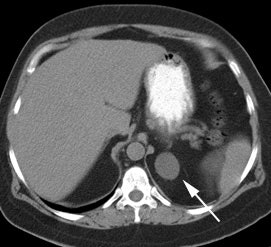

|

Benign adrenal lesion with FDG uptake: The patient shown below had a left adrenal mass which had remained stable for 2 years (white arrow). The stability over time and CT features would be consistent with a benign adrenal lesion- likely an adenoma. Note the marked FDG uptake within the mass on PET imaging (black arrows). Benign adrenal adenomas can accumulate FDG resulting in false positive exams. The use of PET/CT has been shown to improve the specificity of the PET exam. |